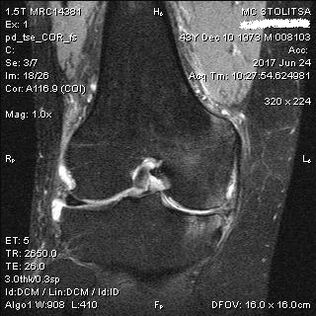

Arthrose de l'articulation du genou en IRM